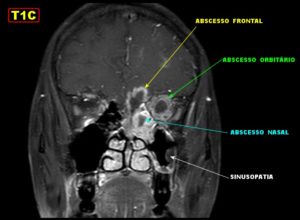

- переход воспаления на глазницу с развитием абсцессов и флегмоны — их лечить только оперативно;

Сфеноидит: фото

Сфеноидит является самым опасным воспалением пазух, если сравнивать его с последствиями воспаления других придаточных пазух носа. Клиновидные пазухи находятся у основания черепа, и гнойное воспаление этих пазух чрезвычайно быстро прогрессирует и вызывает тяжелейшие осложнения.